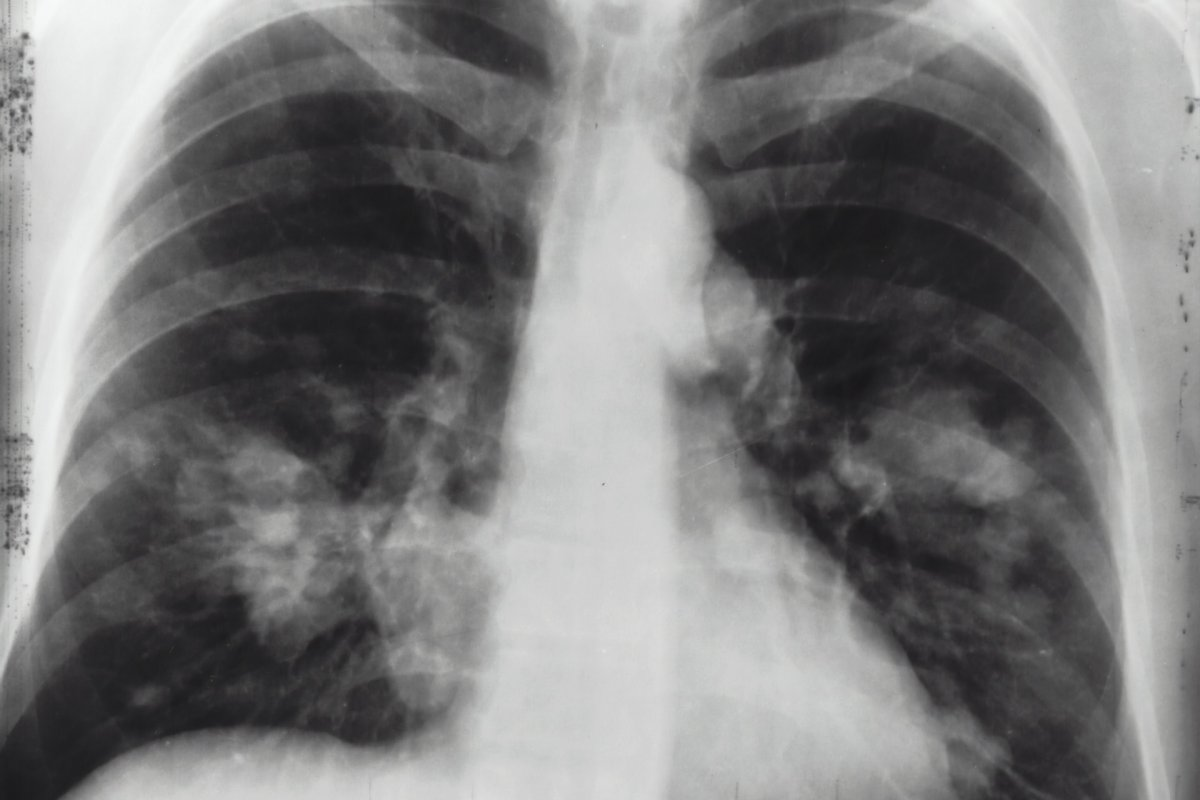

Key Inflammatory Markers on Chest CT Scans

Chest CT scans help find important signs of inflammation. These signs are key to figuring out how severe and what type of inflammation is in the chest.

Ground-Glass Opacities

Ground-glass opacities are often seen on chest CT scans. They show inflammation in the lung’s tissue. These spots are seen in pneumonitis or when an infection is just starting.

Consolidation Patterns

CT scans show consolidation patterns when inflammation is more serious. This means the lung’s airspaces are filled with cells or fluid. It’s seen in pneumonia or acute respiratory distress syndrome (ARDS).

Bronchial Wall Thickening

Bronchial wall thickening is a sign of inflammation. It’s linked to bronchitis or bronchiectasis. This thickening can cause coughing and trouble breathing.

Pleural Effusion

Pleural effusion is when fluid builds up in the pleural space. It’s a big sign of inflammation seen on chest CT scans. It can be caused by infections, cancers, or autoimmune diseases.

Knowing these signs on chest CT scans is vital for correct diagnosis and treatment. By spotting these signs, doctors can give the right treatment for the inflammation.